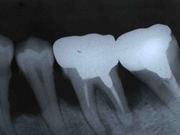

治療前

治療後1年4ヵ月

治療の説明:右下後ろから2番目の歯の骨を再生するため、エムドゲインによる再生療法を行った。歯の根の間の股の部分の再生も確認された。

治療期間:術後1年間ほどレントゲンにて経過観察

治療回数:1回(1時間程度)

治療の料金:77,000円(税込)